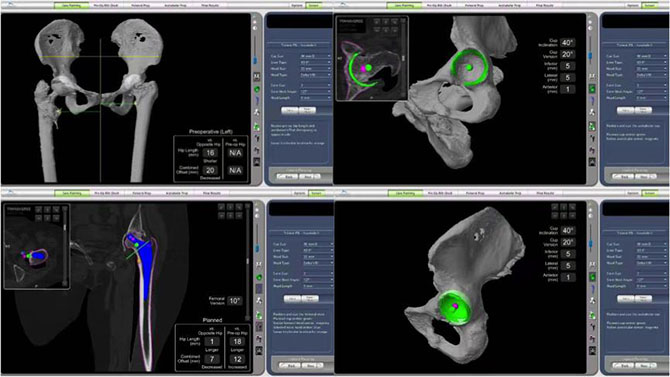

2019年10月,郑秋坚教授团队成功开展了我省第一例MAKO机器人辅助下的人工全髋关节置换手术,这是广东省以至华南地区首例机器人辅助下人工关节置换手术。术中外科医生借助智能导航和机械臂便可准确操作和安放假体。所有参数、角度可精确到0.1毫米级,从而能够达到手术更安全、患者恢复更快、下肢基本等长、脱位更少、人工关节使用时间更长的优异手术效果。